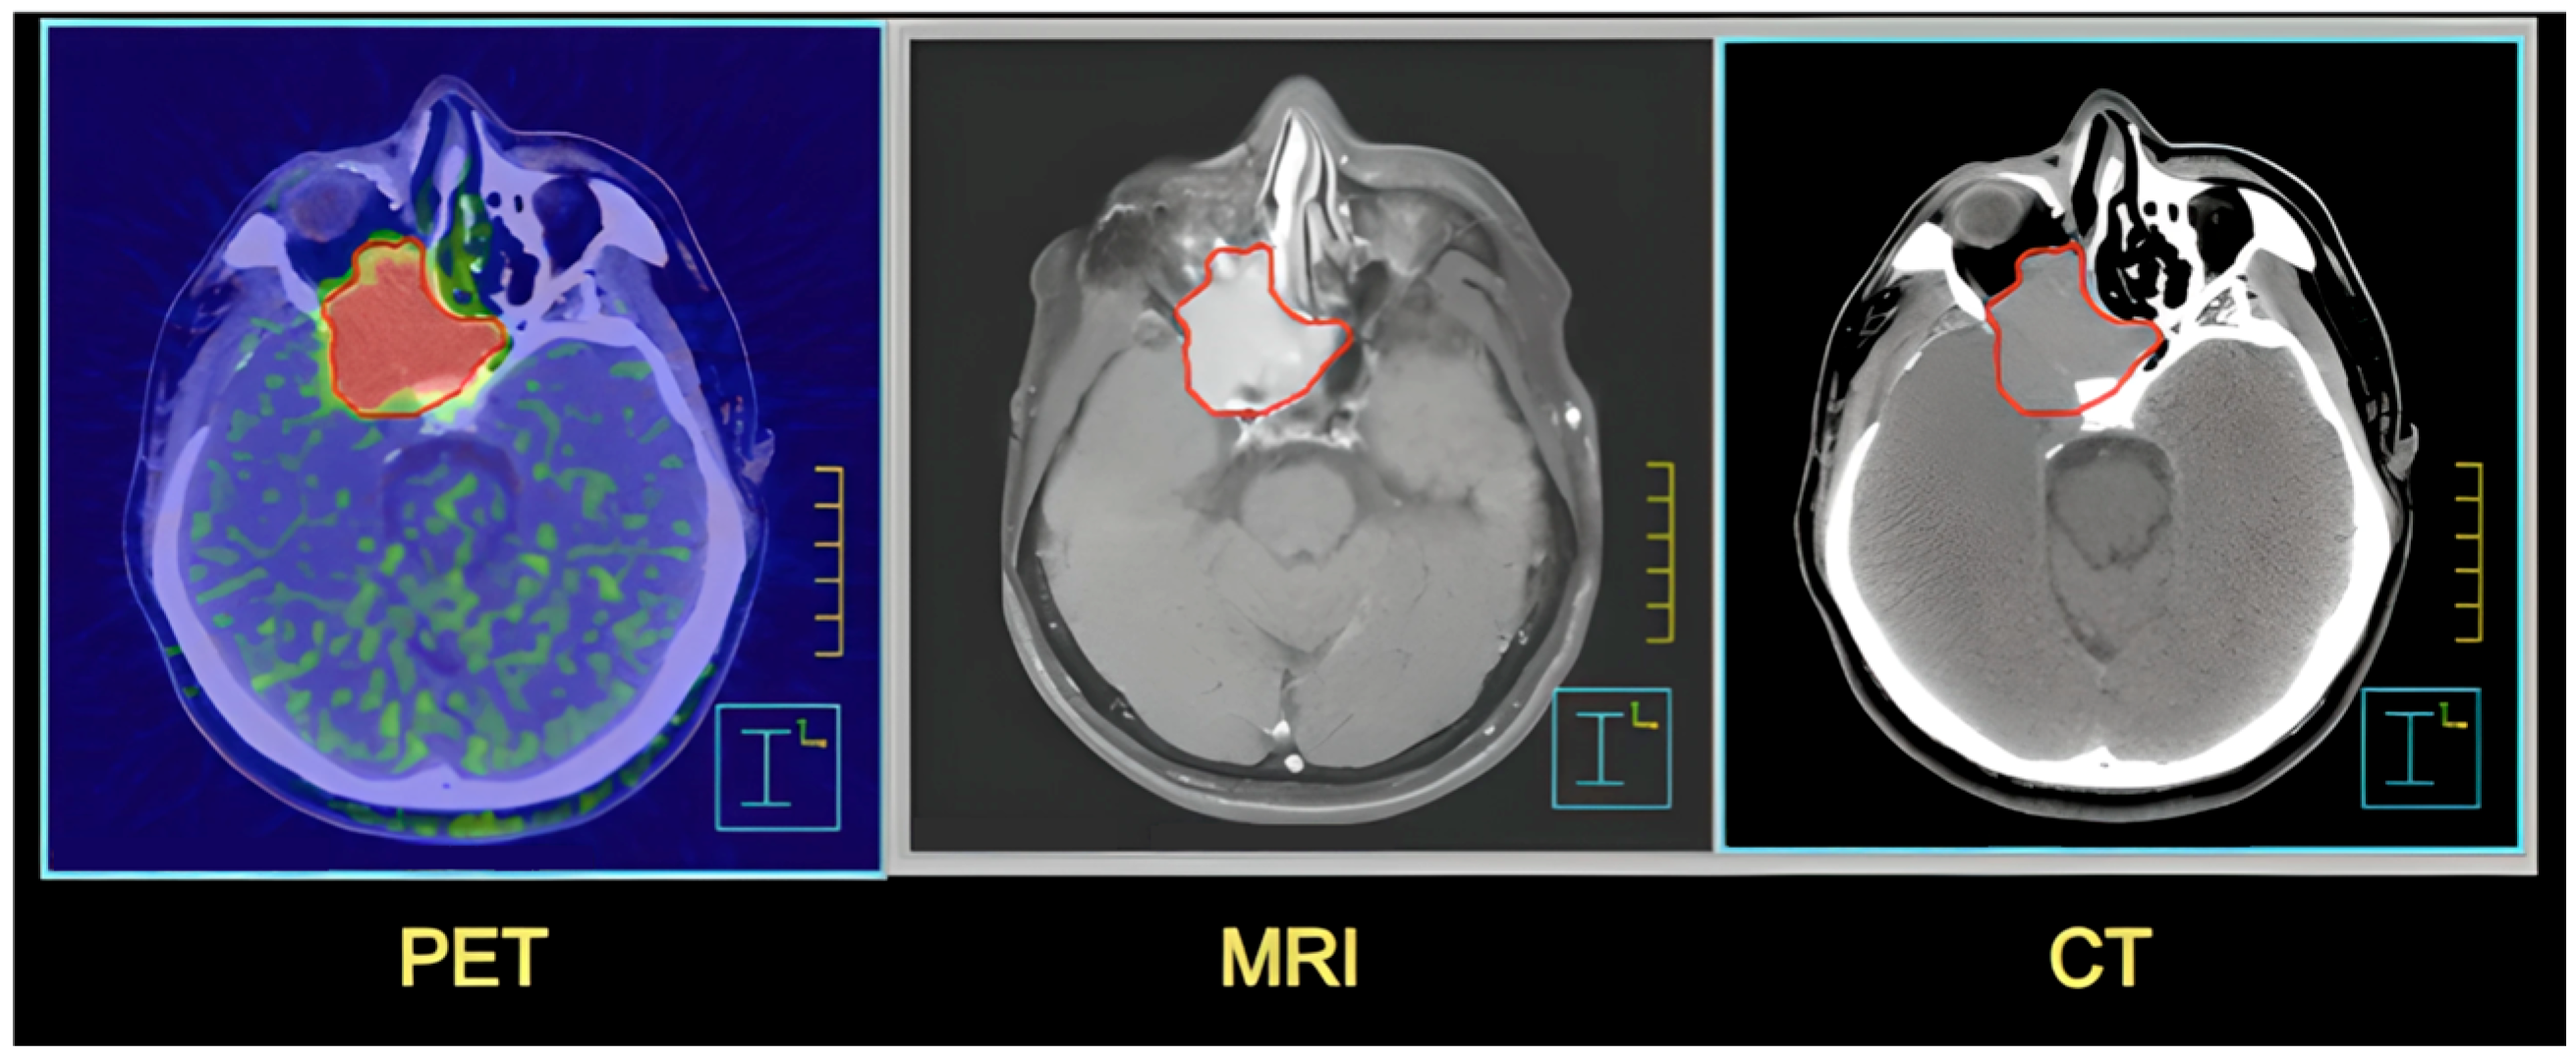

- Huang, G.; Albers, P.; Mookerji, N.; Pfanner, T.; Hui, A.; Mittal, R.; Broomfield, S.; Dean, L.; Martin, B.S.; Jacobsen, N.-E.; et al. Three-dimensional spatial localization and volume estimation of prostate tumors using 18F-PSMA-1007 PET/CT versus multiparametric MRI. Eur. J. Nucl. Med. Mol. Imaging 2025, 52, 1642–1648. [Google Scholar] [CrossRef] [PubMed]

- Vijayakumar, S.; Yang, J.; Nittala, M.R.; Velazquez, A.E.; Huddleston, B.L.; Rugnath, N.A.; Adari, N.; Yajurvedi, A.K.; Komanduri, A.; Yang, C.C.; et al. Changing Role of PET/CT in Cancer Care with a Focus on Radiotherapy. Cureus 2022, 14, e32840. [Google Scholar] [CrossRef]

| Feature | CT | MRI and NMR | PET |

|---|---|---|---|

| Operation principle | X-rays | Magnetic field and radio waves | Radioactive tracer and detection of emitted positrons |

| Applications | Imaging of bone structures, injuries, in emergency situations | Imaging of soft tissues, organs, nervous system, joints (MRI); lab chemical analysis techniques (NMR) | Detection and assessment of metabolic activity in cells, e.g., tumors |

| Safety | Exposure to ionizing radiation | Safer-does not use ionizing radiation | Depends on the tracer used, but generally safe |

| Contraindications | Pregnancy, frequent exposure to radiation bodies | Medical implants, metallic foreign, pacemakers | Specific to the tracer used |

| Examination time | Short (a few to several minutes) | Longer (several to several dozen minutes) | Variable (depends on the examination) |

| Additional comments | Contrast agents: Iodine-based contrast agents are used in CT scans | Gadolinium-based compounds are used in MRI scans | Particularly useful in the diagnosis of oncological diseases, examinations are combined, PET/CT or PET/MRI, to obtain a more complete clinical picture |